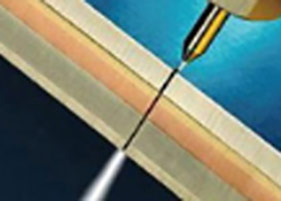

principle and development of water knife technology水刀技术通过独有组织细胞分离技术精准定位大汗腺,由发丝孔径大小的喷嘴喷射超高音速可调控的高压水流,系统采用了文丘里效应,通过无菌生理盐水水流粉碎、回吸异常大汗腺,同步实现安全便捷,术后创口自然美观,30分钟左右快速祛臭。